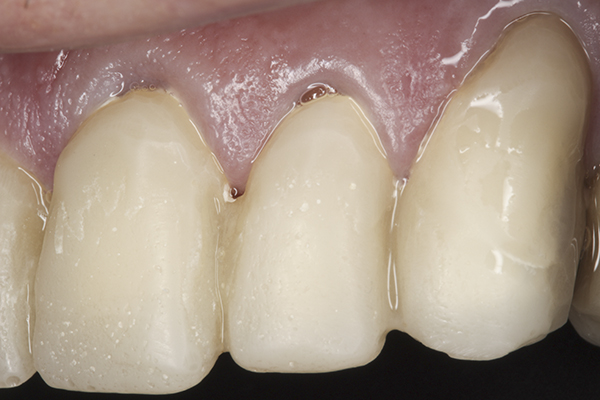

(38.) Postoperative right anterior, close-up view.

Figure 38

(39.) Postoperative anterior, close-up view.

Figure 39

(40.) Postoperative left anterior, close-up view.

Figure 40